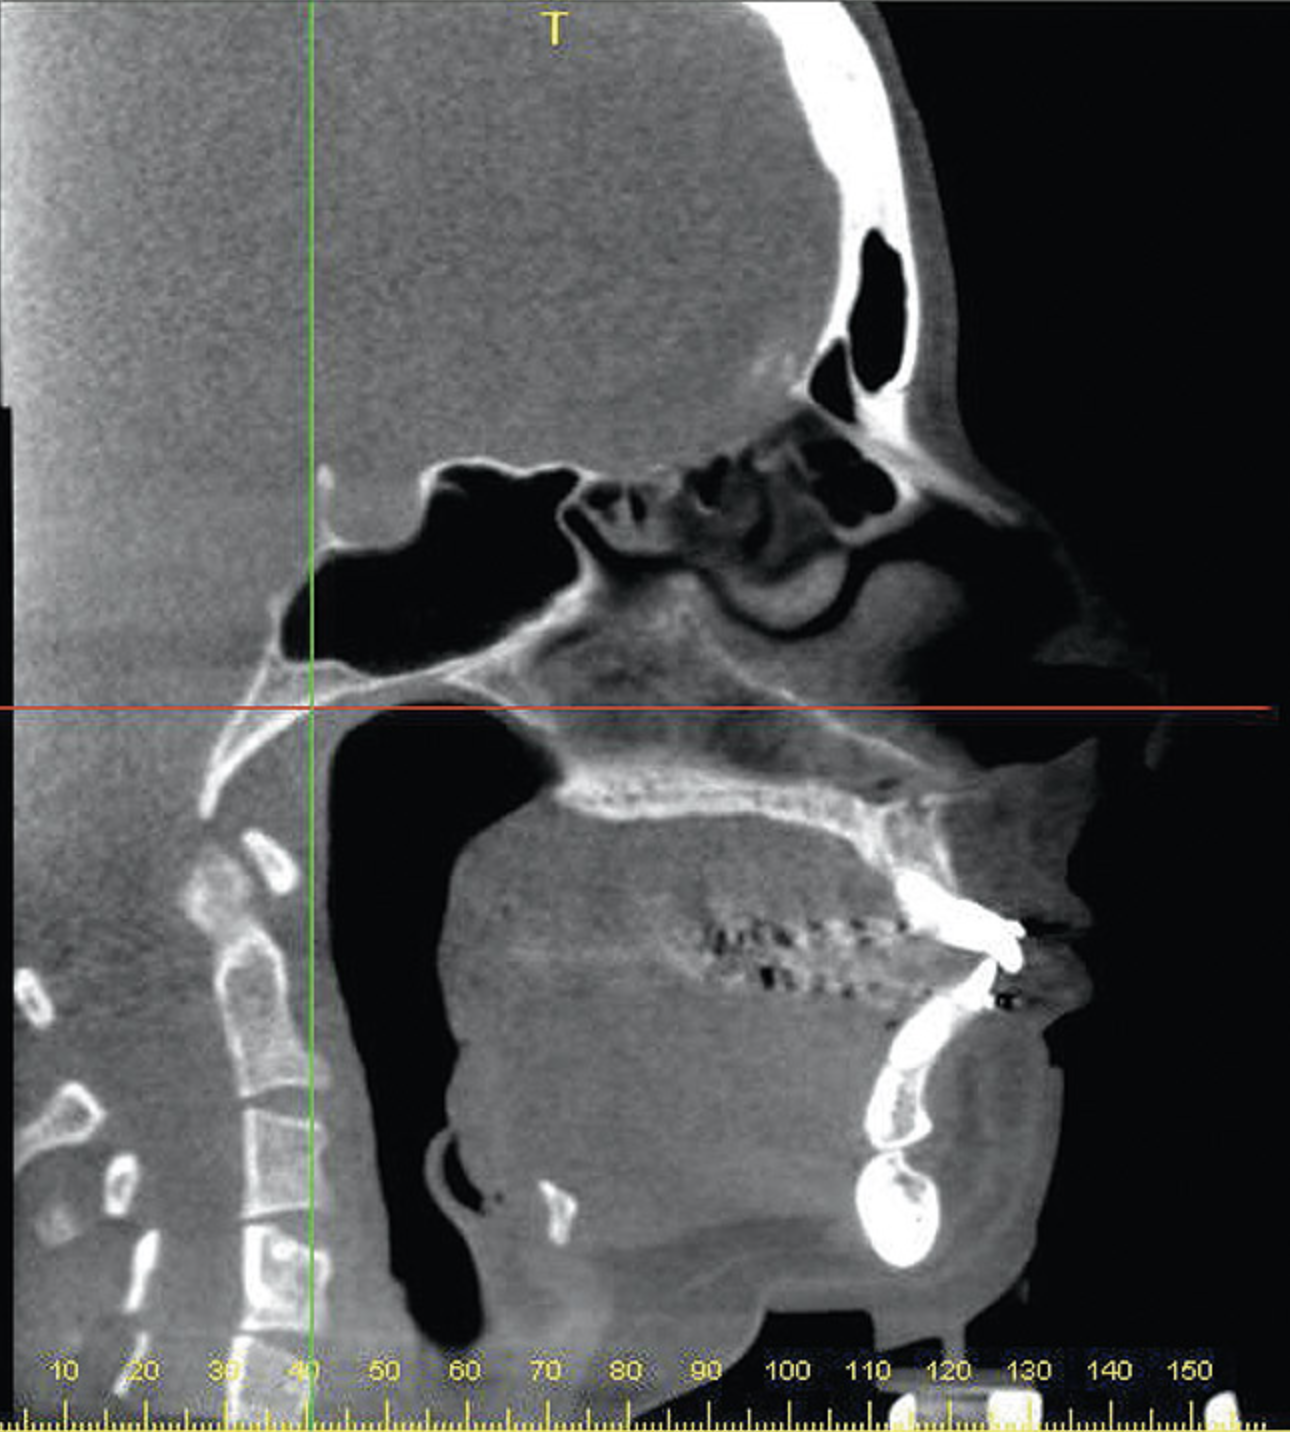

A stable TMJ is critical in establishing a normal functional occlusion. Unless the condyles are in a stable musculoskeletal position, there are always interferences to normal function and stress placed on the masticatory system.1-3,15 In orthodontics, the Angle classification of malocclusion using handheld models has been the standard to evaluate the fit of the teeth. However, it is not possible to truly identify the occlusion/malocclusion using handheld models. Before the occlusion can be evaluated, the clinician must ascertain the joint position and condition (Figure 7 and Figure 8).1,16

Figure 7A  This case is an example of the importance of evaluating the bite with the joints seated in a stable position. Orthodontic treatment was rendered to correct a "deep overbite" and trauma to the maxillary incisors. A) Handheld models in maximum intercuspation at beginning of treatment. The deep overbite is apparent.

Figure 7A

Figure 7B  This case is an example of the importance of evaluating the bite with the joints seated in a stable position. Orthodontic treatment was rendered to correct a "deep overbite" and trauma to the maxillary incisors. B) Handheld models showing correction of the deep overbite after orthodontics has been completed. The patient complained of "jaw" discomfort after orthodontic treatment.

Figure 7B

Figure 7C This case is an example of the importance of evaluating the bite with the joints seated in a stable position. Orthodontic treatment was rendered to correct a "deep overbite" and trauma to the maxillary incisors. C) Models mounted in CR after use of a superior repositioning splint to stabilize the joints. With stabilized joints, the true malocclusion is uncovered. The patient went back into orthodontic treatment and required mandibular advancement surgery.

Figure 7C

Figure 7D  This case is an example of the importance of evaluating the bite with the joints seated in a stable position. Orthodontic treatment was rendered to correct a "deep overbite" and trauma to the maxillary incisors. D) Models mounted in CR after retreatment.

Figure 7D